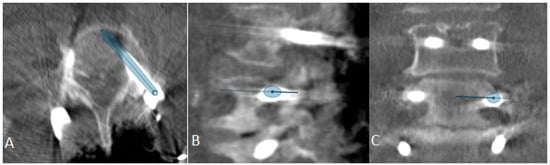

Figure 9. Same patient as in Figure 1, Figure 2 and Figure 7. (A) iCT scan with AI-assisted vertebra recognition. (B) Screw trajectory in the preoperative CT. (C) iCT scan after fusion with preoperative CT shows the screw trajectories, with the option of correcting the screw planning according to the iCT scan.